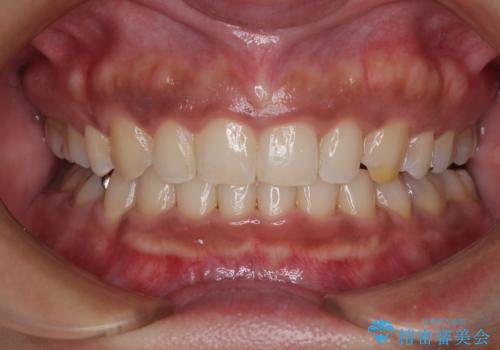

サーフィンで前歯をぶつけて歯が欠けた|かかりつけ医で治療困難と言われ当院へ来院|VPT(生活歯髄療法)で神経を保存|前歯の見た目も改善

[ セラミック治療 ] 前歯の見た目を改善したい

担当医 大元洋佑